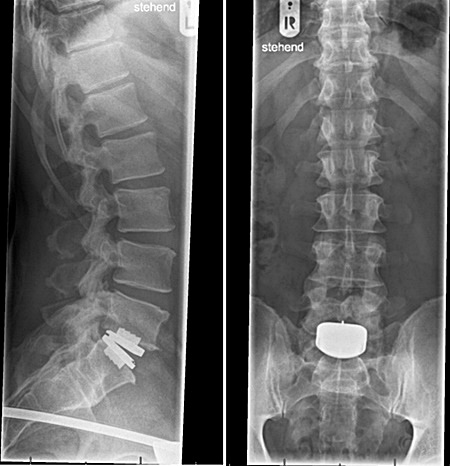

After being ruled

inoperable, my wife and I

traveled to Germany, where

in

May of 2014, I had a

Pro-Disc ADR implanted at my

damaged L5-S1 area, as

illustrated on the right.

American standards only

allowed the

surgical implementation of

one lumbar ADR disc. However, I

had already undergone an

artificial disc replacement

(ADR) for one lumbar disc in

2014,

and it seemed I would now

require a second ADR, as

highlighted in red in the

image on the right.

My only option was again Europe